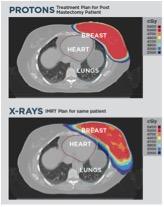

Proton therapy, or proton beam therapy, is a type of radiation therapy used to treat cancer. At a high energy, the positively charged particles can destroy cancer cells.